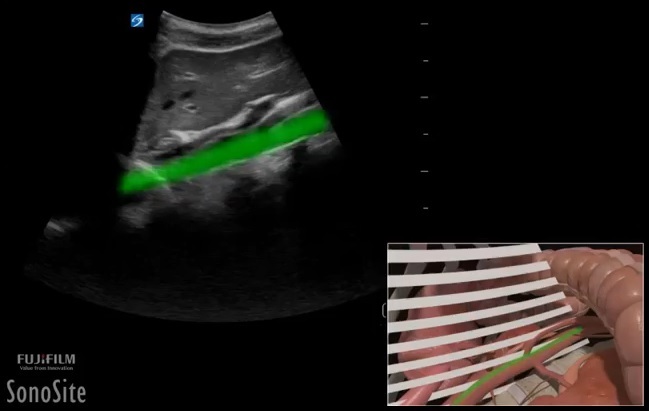

Gastric Content Abdominal Aorta Image